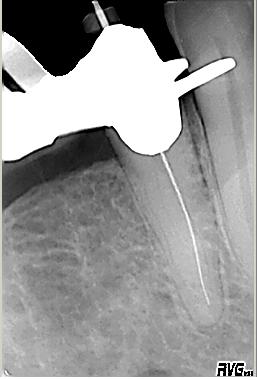

Orientierende Röntgenmeßaufnahme

Orientierende Röntgenmeßaufnahme nach vorgängig durchgeführter endometrischer Längenbestimmung des buccalen Kanalsystems